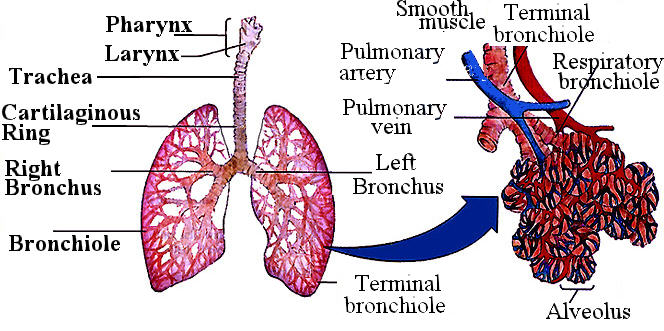

Роль легких в метаболических процессах